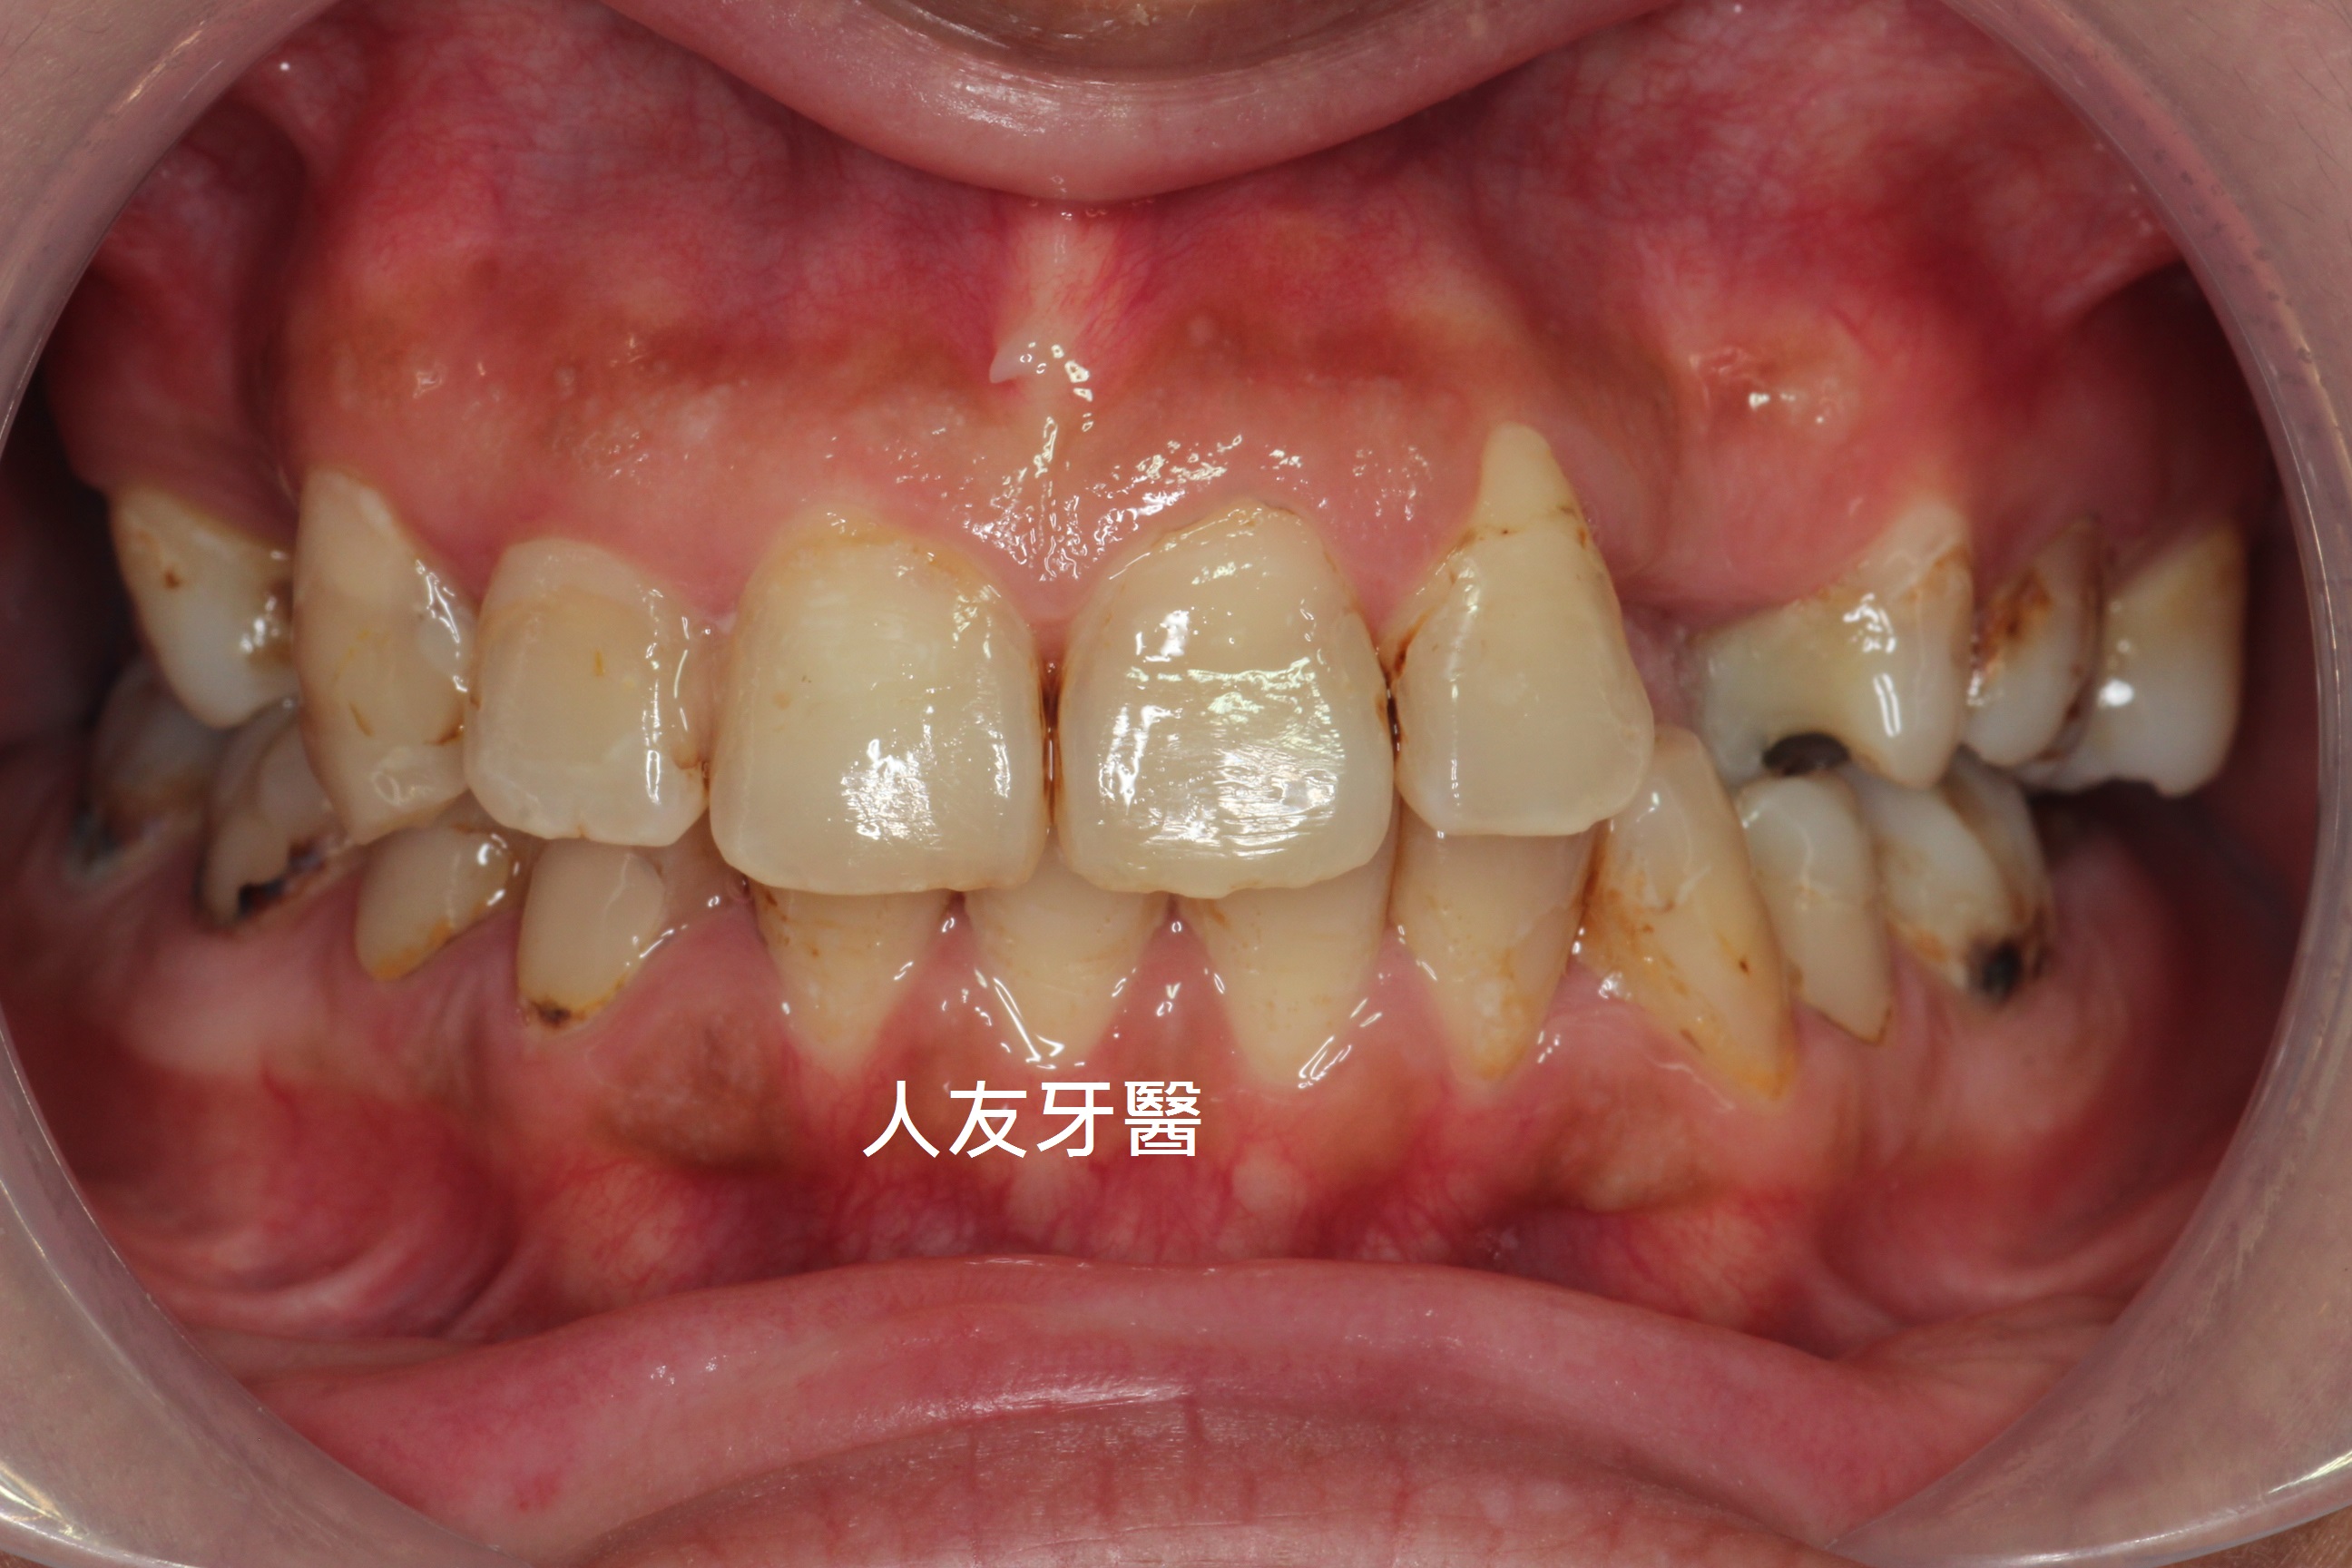

什麼是黑色牙垢

黑色牙垢是一種常見於牙齒表面的黑色條狀著色,通常出現在上顎與下顎的內側牙齒,這類色素不是蛀牙,但清潔困難易影響美觀。

常見特徵

(1)多見於牙齒的齒頸部

(2)一般牙刷難以完全清除

(3)非蛀牙,但若不處理,易藏牙菌斑

案例分享

有一位26歲女患者訴說她以前洗牙很容易敏感、會痠,但經過本診所進行的舒適型噴粉淨白方式,反而讓她驚訝為什麼不會痛、不會痠,甚至可以改善長期下來愛喝茶、咖啡導致的深層茶垢,這是因為我們使用相較於傳統清潔方式不同地方所在。